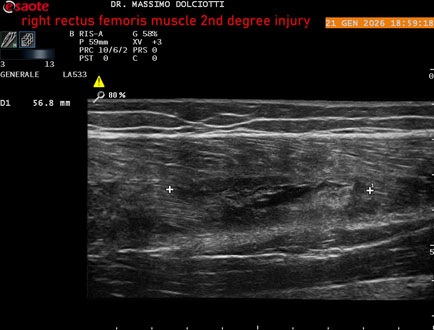

Data inserimento: 23/01/2026

Ecografia del: 21/01/2025

Strumento: Esaote MyLab Eight

Sonda: Lineare Multifrequenza 3-13 MHz

Età Paziente: M 23 anni

Motivazione dell'esame: dolore al terzo prossimale della coscia destra da tre giornii.

Commento all'esame: le immagini ed il video documentano, al terzo prossimale del muscolo retto femorale destro, area disomogenea, ipoecogena, delle dimensioni di 35 mm per uno spessore di 18 mm, misura ottenuta per asse corto o trasversale, e di 71 mm x 20 mm, misura ottenuta per asse lungo o longitudinale, da ricondurre a lesione muscolare di 2° grado con modica raccolta sieroematica intramuscolare.

Conclusioni: lesione di 2° grado del muscolo retto femorale destro (2nd degree injury of the right rectus femoris muscle).